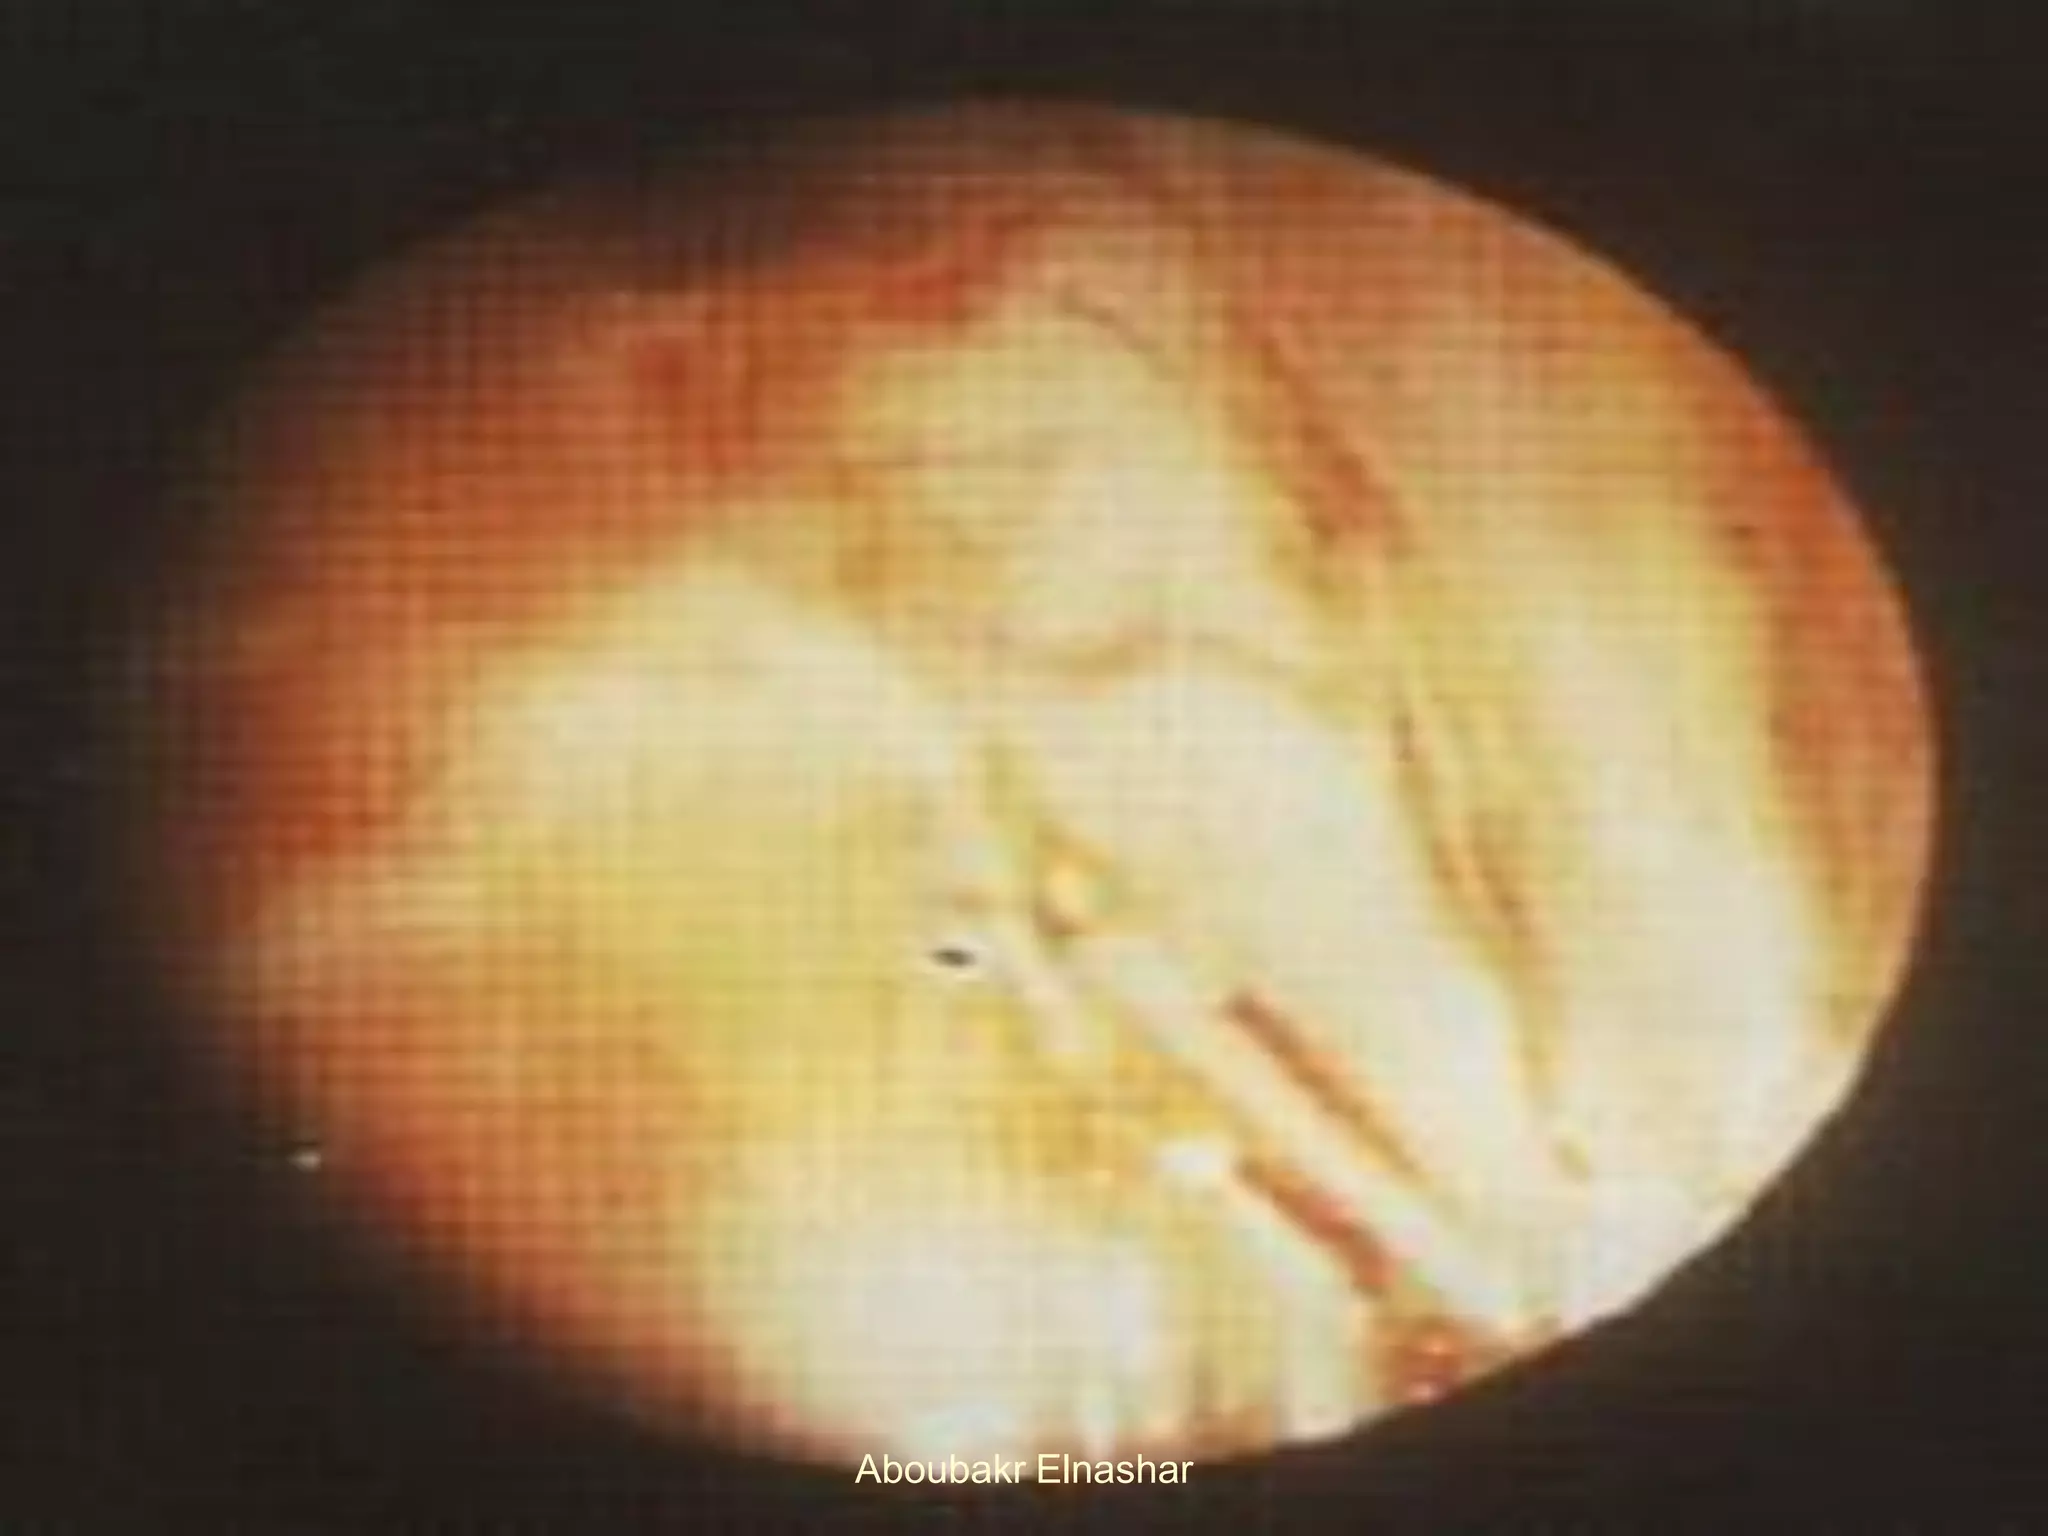

2. Glandular excrescences resemble the mucosal

surface of the endometrium seen at hysteroscopy

Histologically: numerous endometrial glands.